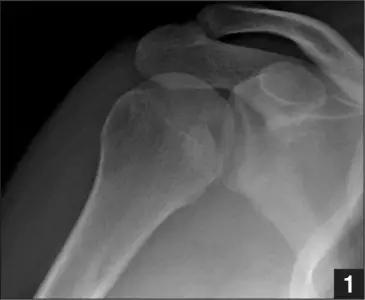

1. Hill-Sachs 损伤和反 Hill-Sachs 损伤

肩关节脱位时,肱骨头和关节盂发生撞击,肱骨头表面凹陷性骨折。

肩关节前脱位时发生的肱骨头后外侧凹陷性骨折,是经典的 Hill-Sachs 损伤(Hill-Sachs lesion);

而肩关节后脱位时发生的肱骨头前内侧凹陷性骨折,是反 Hill-Sachs 损伤(Reverse Hill-Sachs lesion/ McLaughlin lesion)。

正常肩关节(来源:Radiopaedia)

Hill-Sachs 损伤的 X 片(来源:Hill-Sachs Injuries of the Shoulder)